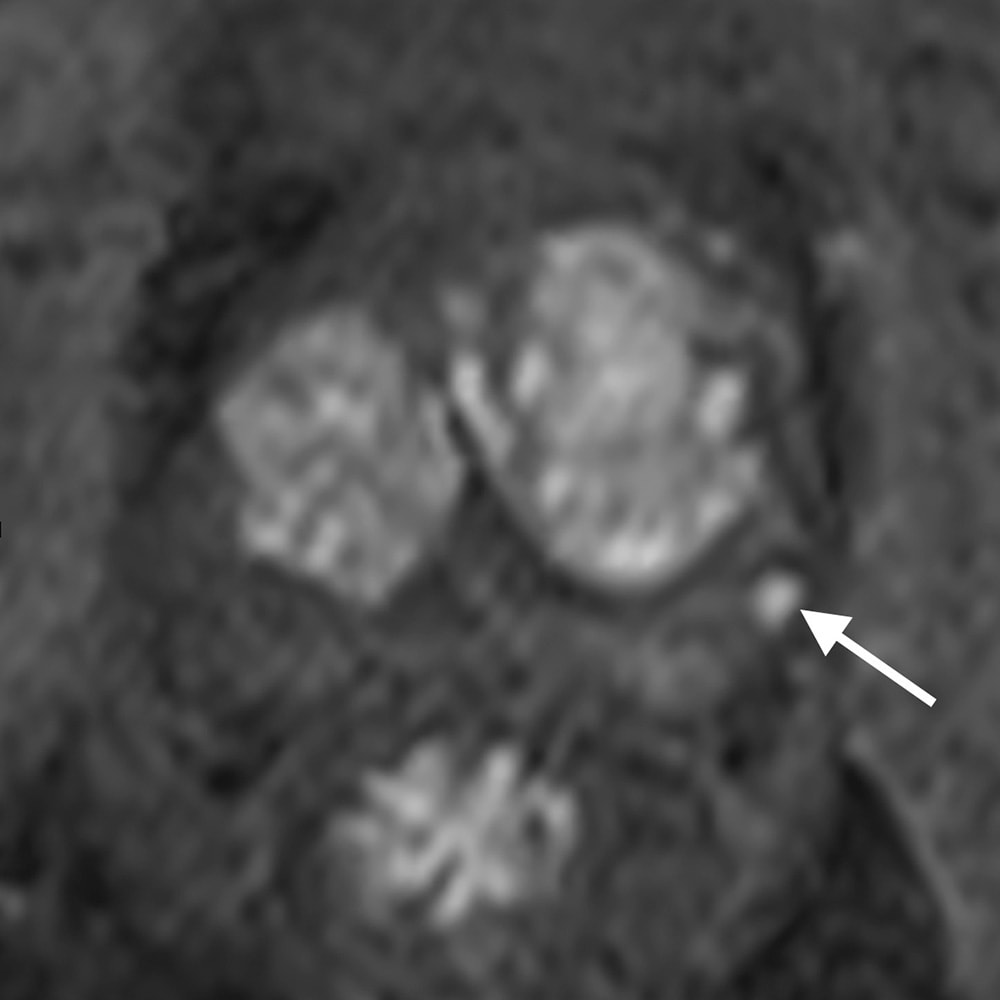

PSA高値(12.4)精査のため施行された1か月前のMRIは、直腸ガス多く、拡散強調画像で一部高信号疑うものの確証が得られなかった。そこで造影検査で再検したところ、微小なPI-RADS4病変が確認された。対象が小さいため、標的生検もふくめて見送り、経過観察している。

当該疾患の診断における造影MRIの役割

PI-RADS (prostate imaging reporting and data system)は、前立腺MRI診断の標準化として泌尿器科医にも広く知られ、前立腺癌診療に欠かせない一部となっている。PI-RADSスコアリングでは、T2強調像と拡散強調像の評価が重視され、造影は補助的な位置づけとなっている。T2強調像と拡散強調像のみを評価するbiparametric MRI (bp-mRI)の診断能が、造影を含めたmultiparametric MRI (mp-MRI)に劣らない、という報告が増え、安易にbi-MRIが多用されるきらいがある。

しかしbp-MRIは拡散強調像に負うところが大きく、拡散強調像は直腸ガスや体動、さらに撮像条件の影響で、安定した高画質を得ることが難しい。これに対し造影ダイナミック撮像は拡散強調像よりアーティファクトの影響を受けにくく、補助的、というよりは実臨床では診断の確診度を高め、フェイルセーフとしての役割が大きい。ガイドライン上も、bp-MRIで評価可能は、3テスラMRIをエキスパートが読影し、標的生検で確認できる施設でのみ、弱く推奨できるとしている。